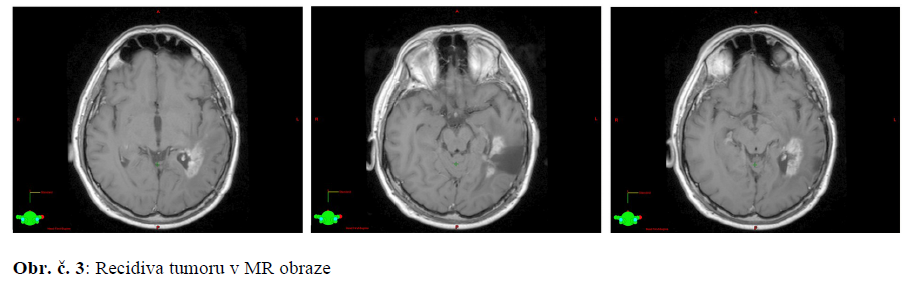

15.5.2014 MR mozku: výrazná multilokulární recidiva tumoru v okolí resekční dutiny vlevo temporálně a nově i na spodině 4. komory, šířící se do pravé mozečkové hemisféry.